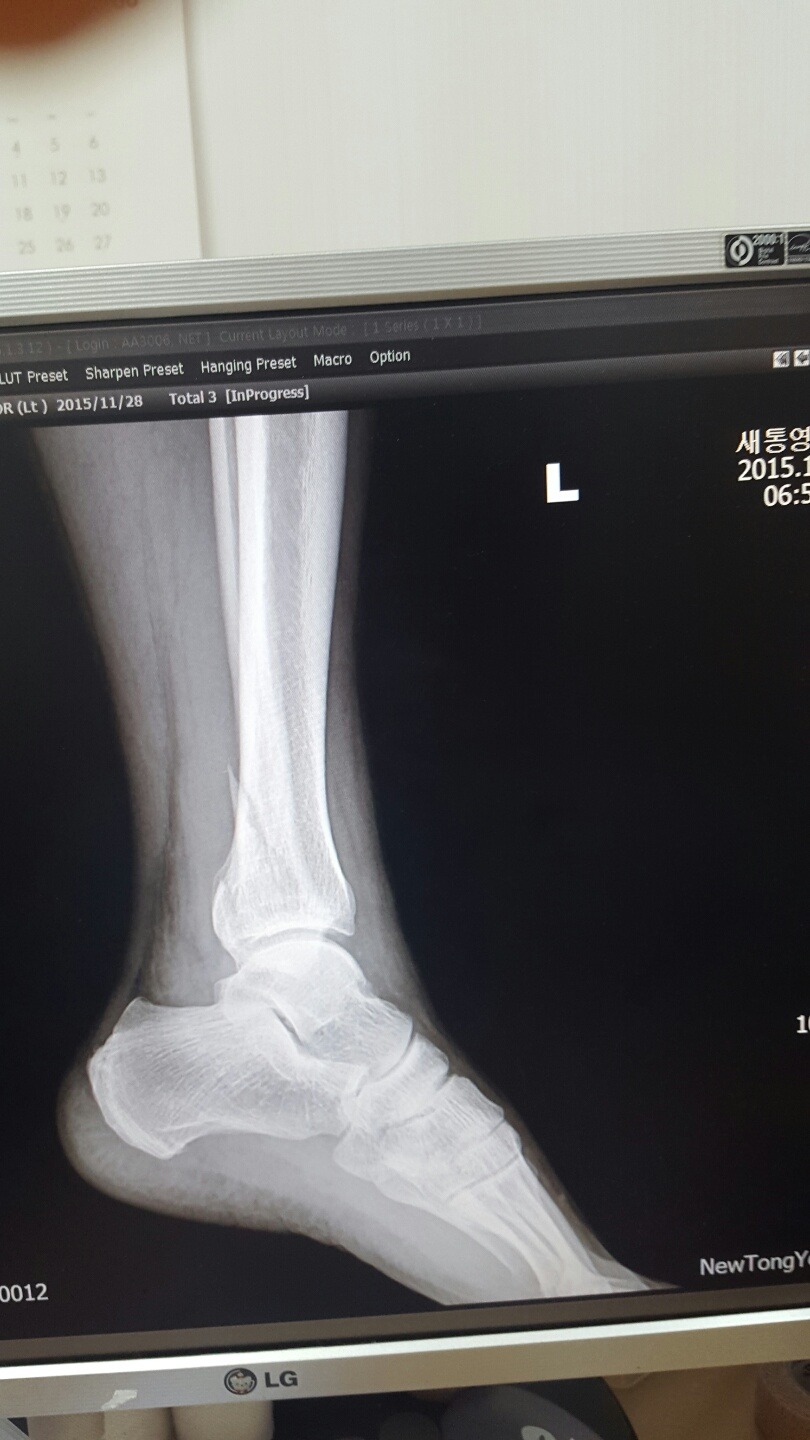

8시30분경 골절사진 촬영 정형외과과장이 경비골골절 탈구(발목이 빠짐)확인. MRI촬영 인대파열확인